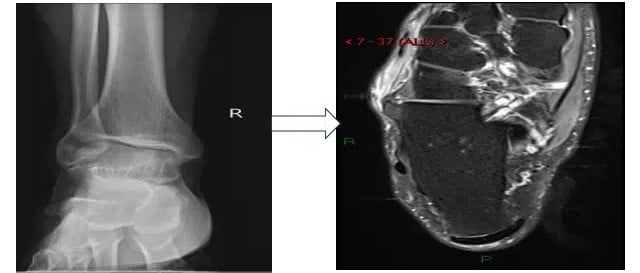

A 49-year-old man presented with complaints of right ankle and mid-foot pain that started during a routine walk. The patient had no history of joint disease or any significant co-morbid conditions, and no history of trauma was given. He underwent a radiograph and an MRI of his ankle. Initial radiograph of the ankle joint, anterior-posterior (AP) view, showed bony growth at the medial aspect of the mid to posterior foot connecting the calcaneum and cuboid bone.

Figure 1: Radiograph and MRI findings of calcaneocuboid coalition

The coalition between the calcaneum and the cuboid is very rare, and we could find only 1 case report of this coalition so far. It occurs more often in association with other anomalies of the foot rather than in isolation. It is an important roentgenographic feature of type I acrocephalosyndactyly (Apert’s syndrome). Craig reported a case of Crouzon’s syndrome (a craniofacial dysostosis) which showed associated bilateral isolated calcaneocuboid synostosis.[5] Radiographic findings of tarsal coalition depend upon the tissue bridging between bones, with a large bony bar seen in the case of osseous coalition, whereas in fibrous coalitions, there is irregularity of bony interface, subchondral changes, and even joint space loss. Often, CT and MRI are used due to the lower sensitivity of radiography. MRI can help to distinguish between types of coalition.[6]